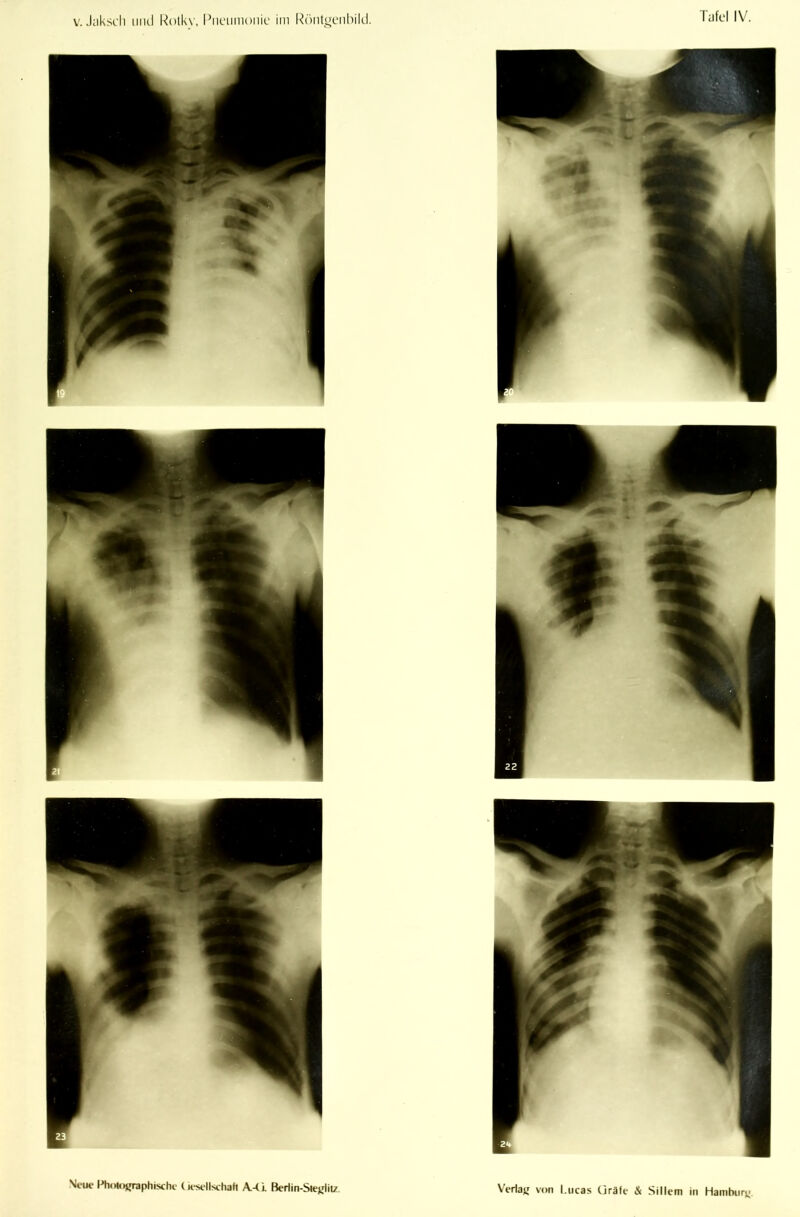

Die Pneumonie im Röntgenbilde ... : mit 59 Röntgenbildern auf 10 Tafeln und 10 Skizzenblättern / von R.v. Jaksch und H. Rotky.

Credit: Die Pneumonie im Röntgenbilde ... : mit 59 Röntgenbildern auf 10 Tafeln und 10 Skizzenblättern / von R.v. Jaksch und H. Rotky. Source: Wellcome Collection.